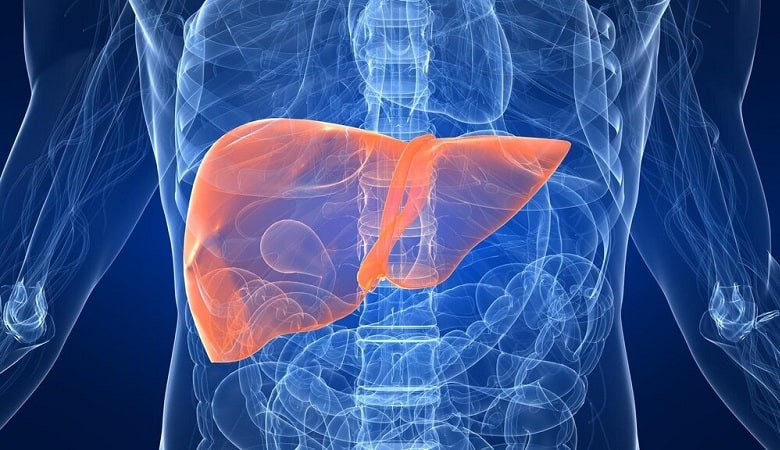

به گزارش وقت صبح به نقل از همشهری آنلاین، ایرج خسرونیا، متخصص داخلی درباره «نشانههای ابتلا به کبد چرب»، گفت:

این بیماری در اوائل هیچ نشانی ندارد اما سستی، بیحالی، ضعف عمومی، خارش بدن و جوش زدن از علائم آن است.

وی ادامه داد: بیشتر به طور تصادفی پیدا میشود؛ یعنی فرد به سونوگرافی میرود و به وی اعلام میشود دچار کبد چرب است.

این متخصص داخلی افزود: تا ۵۰ سال پیش خیلی کبد چرب وجود نداشت اما متاسفانه با توجه به رژیم غذایی غلط و پر چری، عدم تحرک باعث ابتلا به کبد چرب شده است.

نکته شگفتانگیزی که در خلقت این عضو بدن وجود دارد این است که کبد نقش باز ترمیمی بالایی هم دارد و در صورتی که ما فشار خارجی غیر طبیعی به آن وارد نکنیم با قدرت به حمایت از ما ادامه میدهد اما اگر این فشار اضافه و دائمی آن را دچار مشکل کند، ما دچار کسالت خواهیم شد.